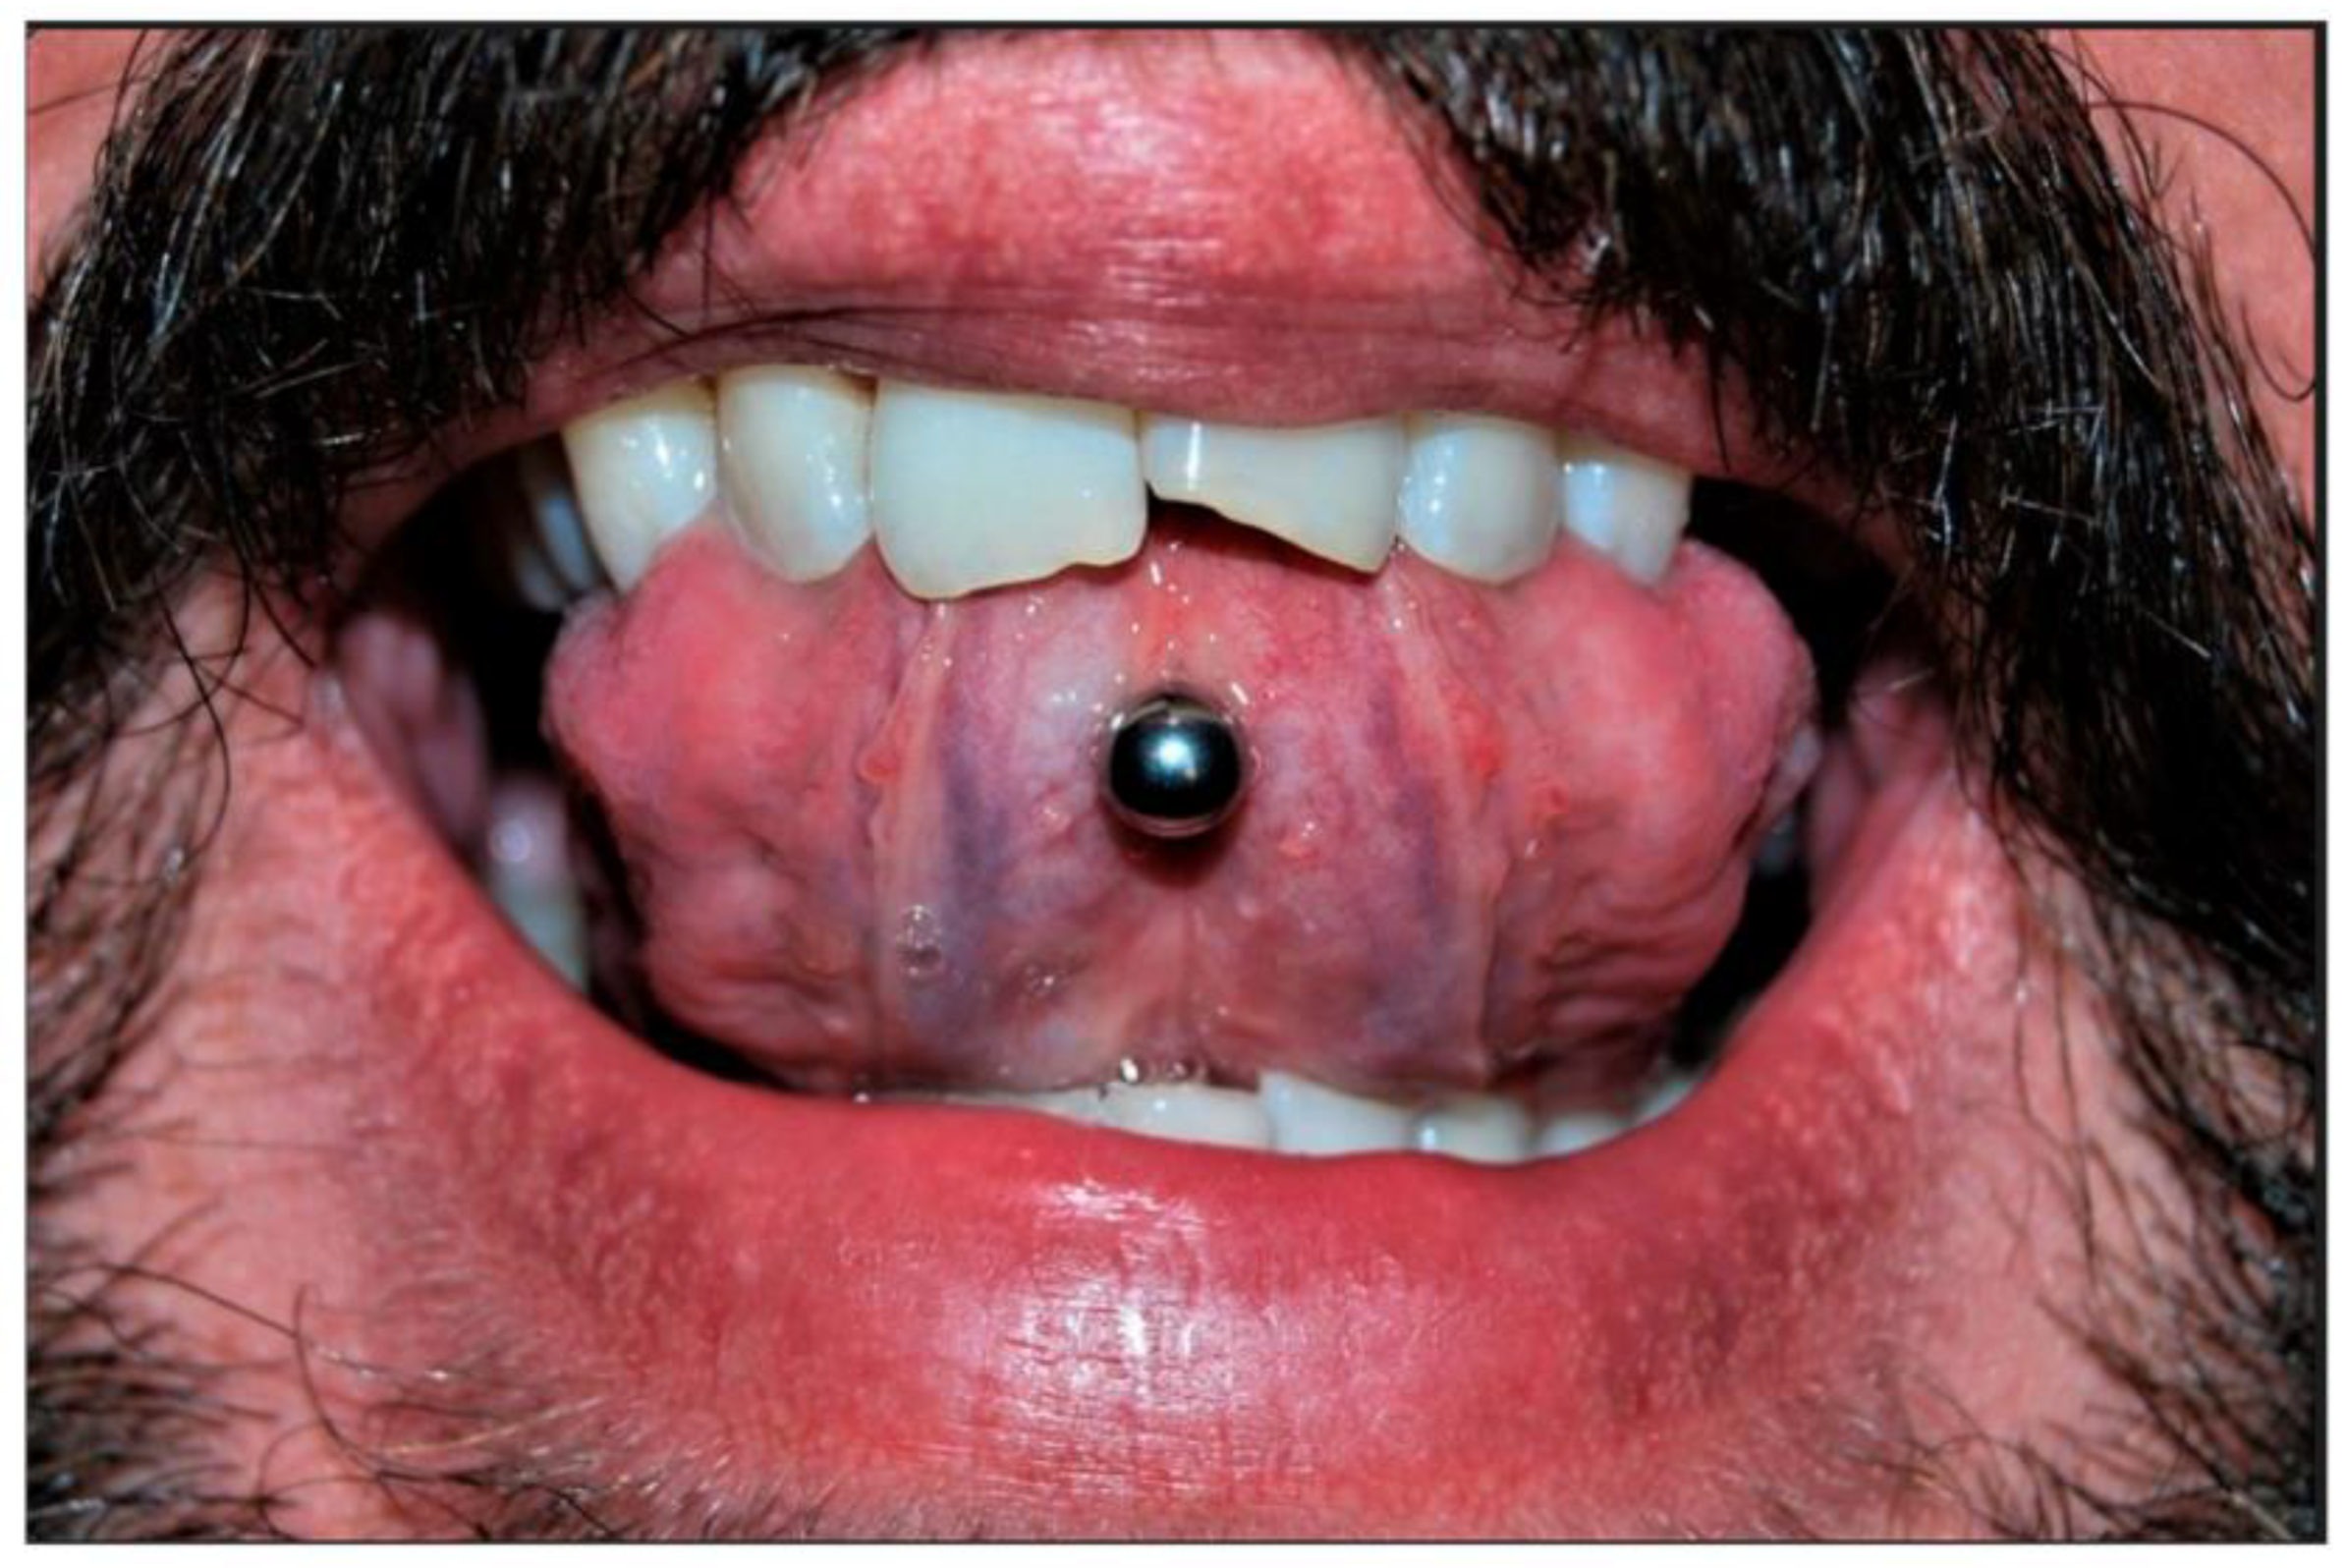

Figure 4.

Piercing-associated gingival recession at the labial side of the mandibular anterior teeth [54].